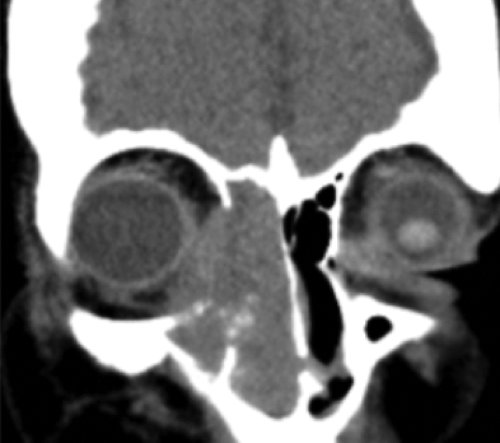

Figure 1: CT of lesion: transverse and coronal views.

The patient was further investigated with CT head and orbits. The scan showed an intraorbital soft tissue mass with extension into the right maxillary, sphenoid and ethmoidal sinuses and into the medial orbit (Figure 1). A biopsy of the right nasal mass was taken and reported as large cell non-Hodgkin’s lymphoma on histopathology examination. The patient underwent CHOP chemotherapy (cyclophosphamide, doxorubicin, vincristine, prednisone) followed by local radiotherapy.